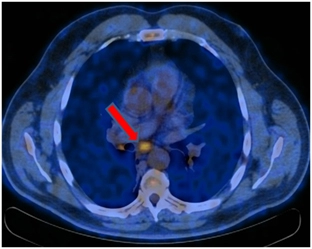

ПЭТ/КТ 04.08.2017. На момент исследования по данным ПЭТ/КТ с 18F-ФДГ признаков патологического метаболически активного процесса, обусловленного основным заболеванием не выявлено.

Постлучевой фиброз, ателектаз нижней доли правого легкого.

Умеренно выраженный правосторонний гидроторакс (увеличение в динамике).

Метаболически активного процесса в кардиальном отделе пищевода на момент исследования не выявлено.